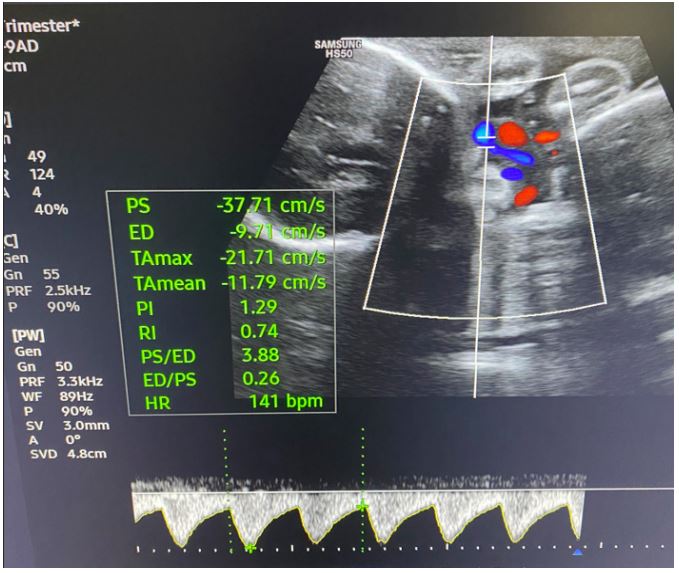

Transabdominal ultrasound identified intrauterine MCMA twin pregnancy. The right ovary measured 14x6.5x9.7 cm with multiple peripherally displaced ovarian follicles resembling a string of pearls (Figures 3 and 4). The left ovary measured 12x7x9.1 cm also with peripheral follicles and stromal oedema (Figure 5). In both ovaries, there was an absent doppler flow. In the region of the right adnexa, there was a collection of free fluid up to 8 mm (Figure 3). Umbilical arterial (UA) Doppler assessment was used in the surveillance of fetal well-being, which showed good fetal condition (Figures 6 and 7).

Figure 6: Umbilical arterial (UA) Doppler assessment of the first twin shows good fetal condition.

Figure 7: Umbilical arterial (UA) Doppler assessment of the second twin shows good fetal condition.